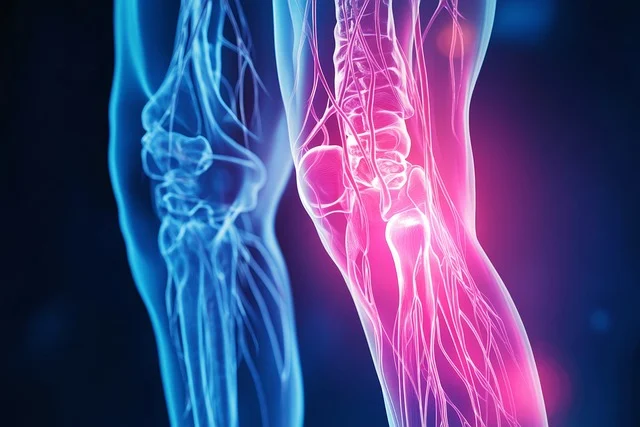

콘드로이친 역할.

⦁ 콘드로이친은 손상된 연골이 일부 재형성되도록 하는데 도움을 줄 수 있습니다

⦁ 관절에 통증이 개선되고 운동 능력이 향상되고 있습니다.